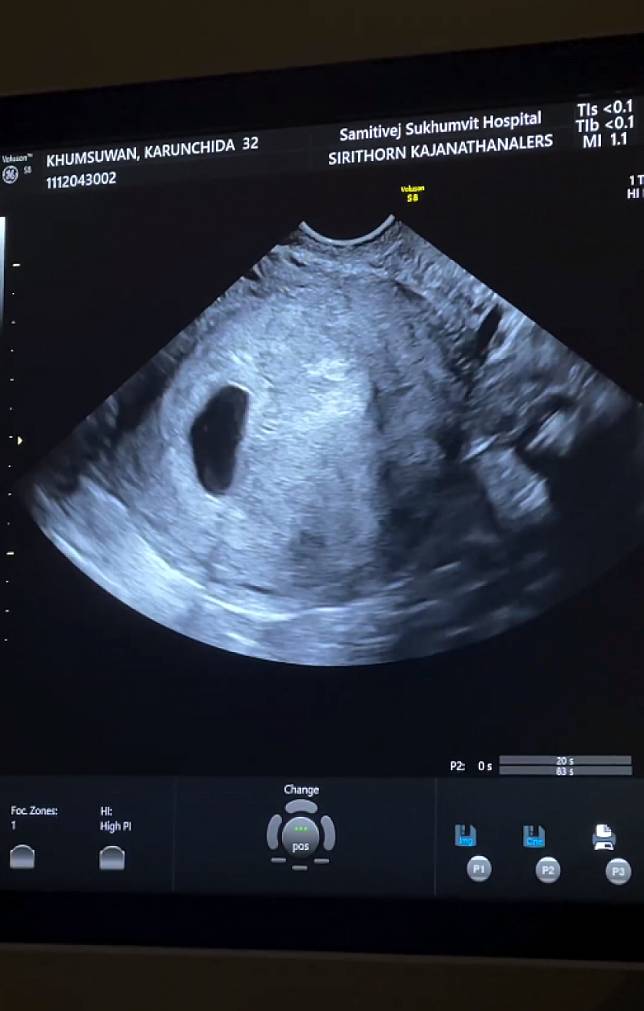

ตื่นเต้นมากที่ได้เป็นพ่อและแม่คนใหม่ของคู่ พราวฟ้า กรชิดา และสามี เสี่ย โบ๊ท ณัฐเดช